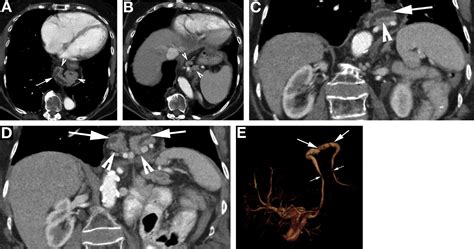

Because the pancreas is deep within the abdomen, doctors rely on advanced imaging techniques to visualize the ducts clearly. If you present with symptoms or if a routine ultrasound shows pancreatic duct dilation, your physician may order one or more of the following tests:

Endoscopic Ultrasound (EUS) Provides high-resolution images; allows for biopsy if a mass is suspected.

Computed Tomography (CT) Scan Useful for rapid assessment and identifying large masses or calcifications.